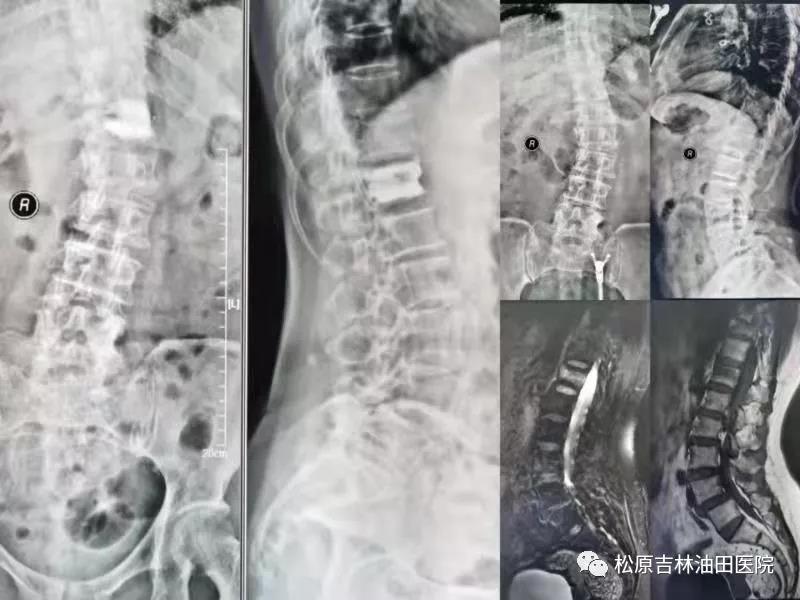

90岁老爷爷术后影像显示:骨水泥良好的弥散和支撑

患者**苹 术后影像(骨水泥得到良好弥散、填充、支撑)与术前影像对比